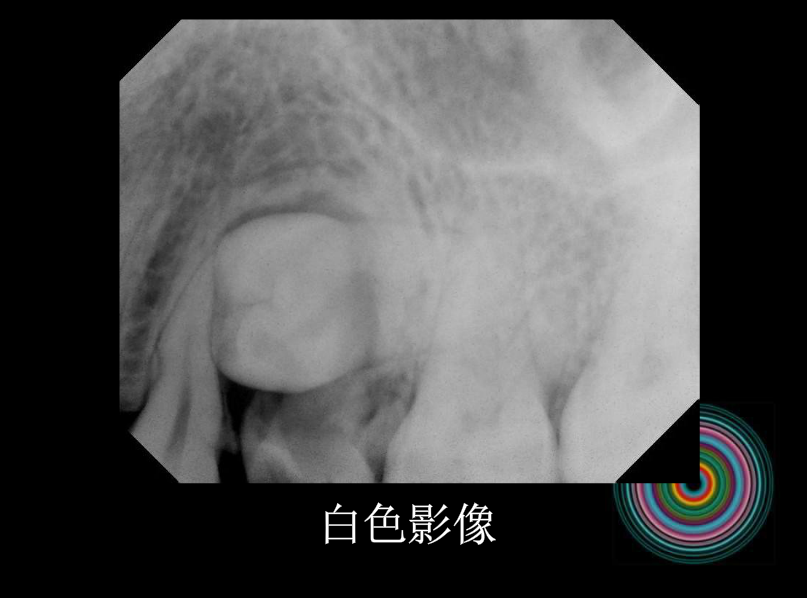

口腔頜面外科 影像技術(shù)